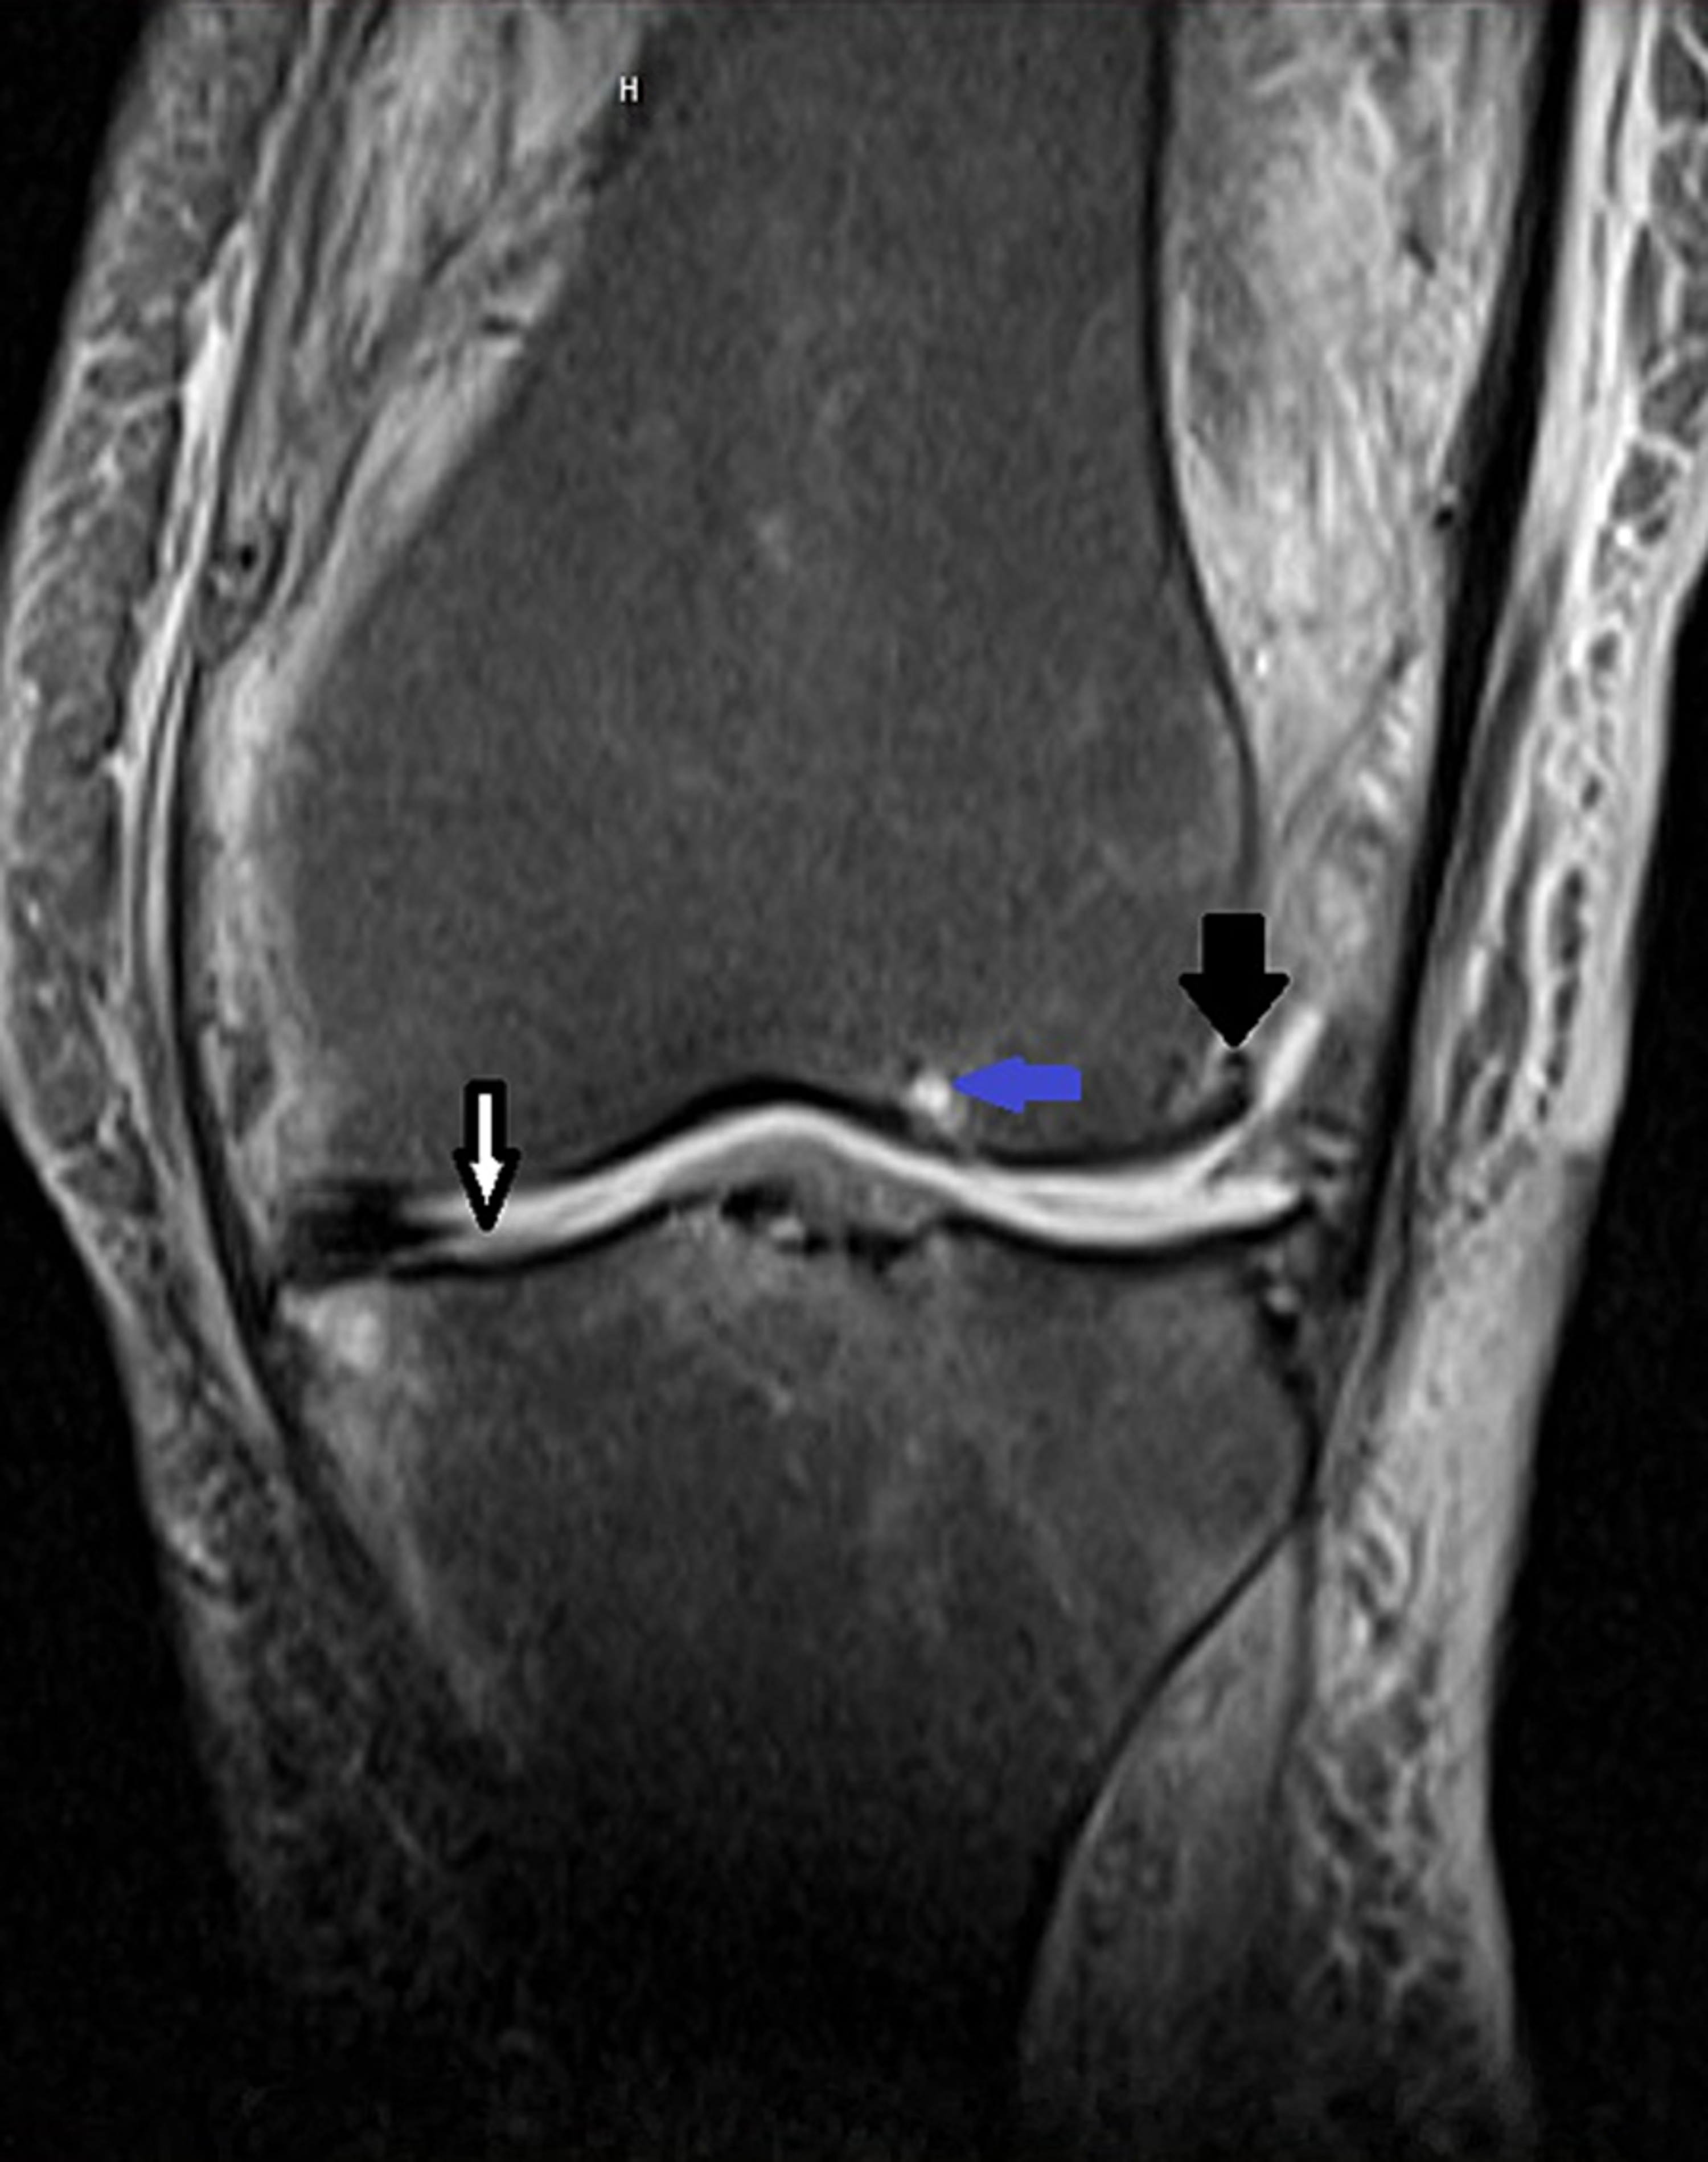

From www.researchgate.net

This anteroposterior radiograph of a knee 6 years after second revision... Download Scientific Scraped Knee Sepsis if the infection that caused your septic arthritis is not treated, the infection can spread to other parts of your body. native joint infections most commonly occur in the knee, followed by the hip, shoulder, ankle, elbow, and wrist. septic arthritis is a painful infection in a joint that can come from germs that travel through your. Scraped Knee Sepsis.